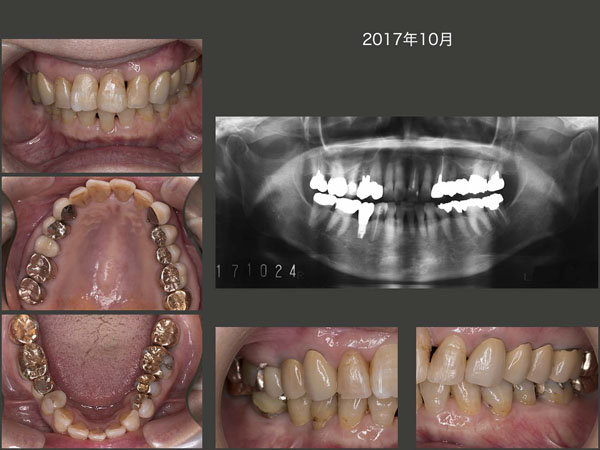

2013年9月,左上1に歯肉膿瘍が生じた.遠心の歯周ポケットが10mm認められた.また歯髄反応は弱く根尖病巣も疑った.まず,抜髄して自然挺出を行う治療計画を立てた.なお,最初浸潤麻酔なしで削去したが,ある程度進んだところで疼痛を訴えたため,歯髄は失活していなかった.そうなると,診断は歯周病となる.また,抜髄後3ヵ月経過をみたが挺出量も少なく,力の関与も低いと思われた.なぜこの歯が急に増悪したのかはよく分からないが,もしかすると歯科矯正を行ったことが関わっているのかもしれない.また,結果からみると抜髄する必要はなかったのかもしれない.

14年2月,歯周外科処置を行った.唇側から遠心にかけて歯槽骨が失われていた.